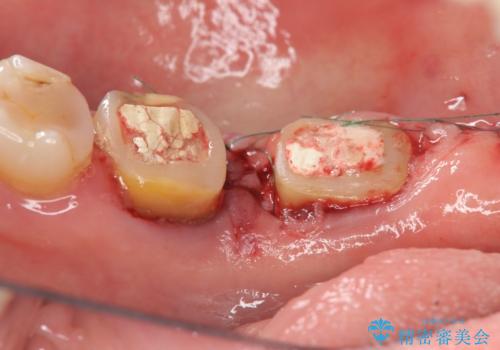

歯周病の歯を残すための再生治療

- 銀歯や虫歯の治療を希望され来院されました。

治療前にX線写真や歯周病検査を行ったところ、中等度に進行した歯周病が見つかりました。

抜歯も検討されるような骨の形態ではありますが、歯周病により溶けてしまった骨を再生させる歯周病再生治療を行うこととしました。

1年間他の治療を行いながら待ったのち、骨の状態確認を行う確定外科の際にしっかりと骨の再生が認められました。